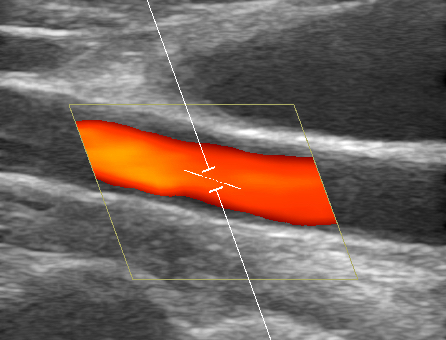

Gefäßdarstellung mittels Ultraschall

Bei der Doppler-Duplex-Sonographie der Halsgefäße wird untersucht, ob Verkalkungen (Plaques) vorliegen, und ob es dadurch zu Verengungen (Stenosen) kommt.

Neben dem Aussehen der Plaques wird die lokale Flussgeschwindigkeit des Blutes beurteilt: Je schneller die Flussgeschwindigkeit, desto hochgradiger die Stenose.